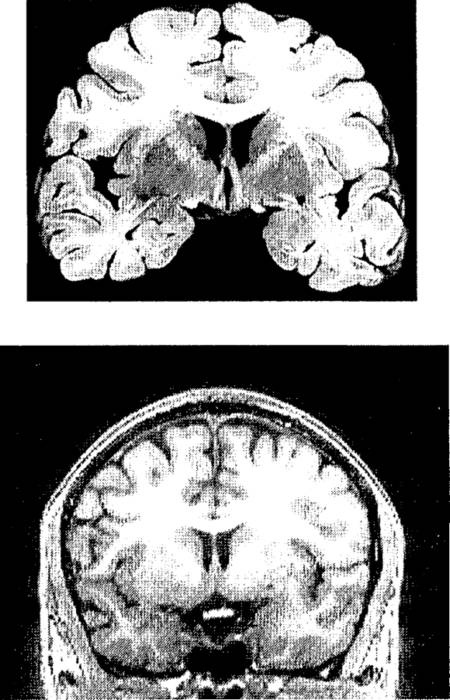

Рис. п.2. Пример полученного с помощью МРТ структурного изображения мозга и срез мозга, извлеченного из трупа.

Вверху – фотография одного из срезов мозга, извлеченного из черепа после смерти и нарезанного тонкими слоями. Внизу – изображение одного из слоев мозга живого человека, полученное методом магнитно-резонансной томографии (МРТ).

Через несколько лет был разработан другой метод, еще лучше прежнего, – магнитно-резонансная томография (МРТ). В МРТ используются не рентгеновские лучи, а радиоволны и очень сильное магнитное поле.[15]В отличие от рентгеноскопии эта процедура совершенно не опасна для здоровья. МРТ-сканер намного чувствительнее к различиям плотности, чем АКТ-сканер. На изображениях мозга живого человека, получаемых с его помощью, различимы разные типы тканей. Качества таких изображений не ниже, чем качество фотографий мозга, после смерти извлеченного из черепа, законсервированного химикатами и нарезанного тонкими слоями.